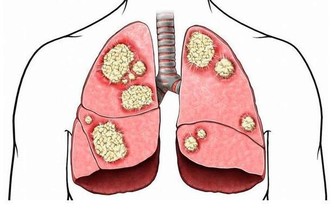

吃太多糖直接增加心臟病風險

。哈佛大學內科醫學教授安東尼.克摩洛夫指出,糖雖然不直接傷害心臟,

但增加心血管疾病風險,升高心臟病機率。